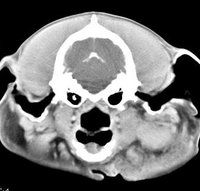

Diagnóstico neurológico | ||||||||||

imágenes de TC en el perro | ||||||||||

ejemplo de imágenes de TC en el perro. Nótese la celulitis en la región parotídea izquierda | ||||||||||